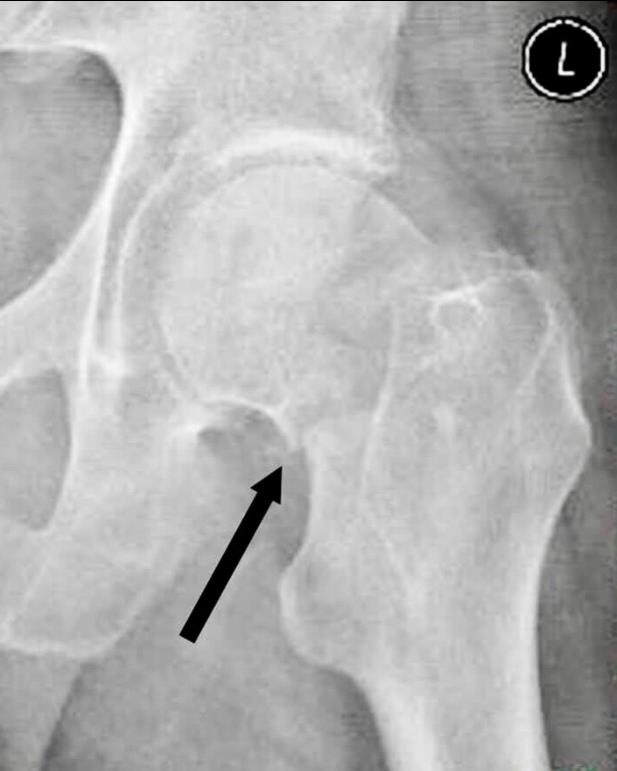

阳性支撑与阴性支撑

1、阳性支撑是指股骨颈骨折的远骨折端突向近侧骨折断端内下缘的内侧。

图3 阳性支撑更稳定

2、阴性支撑是指近侧骨折断端(股骨颈、头)的内下缘突向股骨颈远骨折端内上缘的内侧。阴性支撑容易导致复位的股骨头移位,继而发生内翻,内固定失败率高。

图4 阴性支撑不稳定